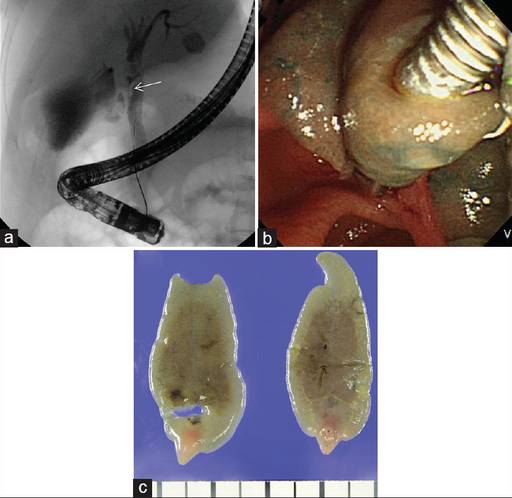

Hình 4